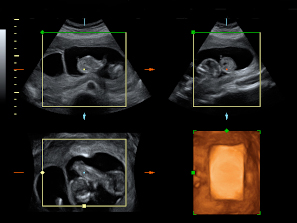

Ecografía de gemelos "jugando" con el cordón umbilical

El movimiento de gemelos en el útero encierra sorpresas, como en esta ecografía 4D en la que vemos a dos hermanos en sus respectivas bolsas. El gemelo de la derecha parece estar bailando el "hula hoop" con su propio cordón umbilical, que le rodea las piernas formando un círculo. Destaca la posición casi erguida del niño dentro del útero materno, casi a punto de dar un paso. Cuando uno de los fetos genera mucho movimiento, suele arrastrar a su gemelo a que se mueva también, aunque esté adormecido.

Ecografía 4D de gemelos de 12 semanas moviéndose: el baile del "hula hoop"